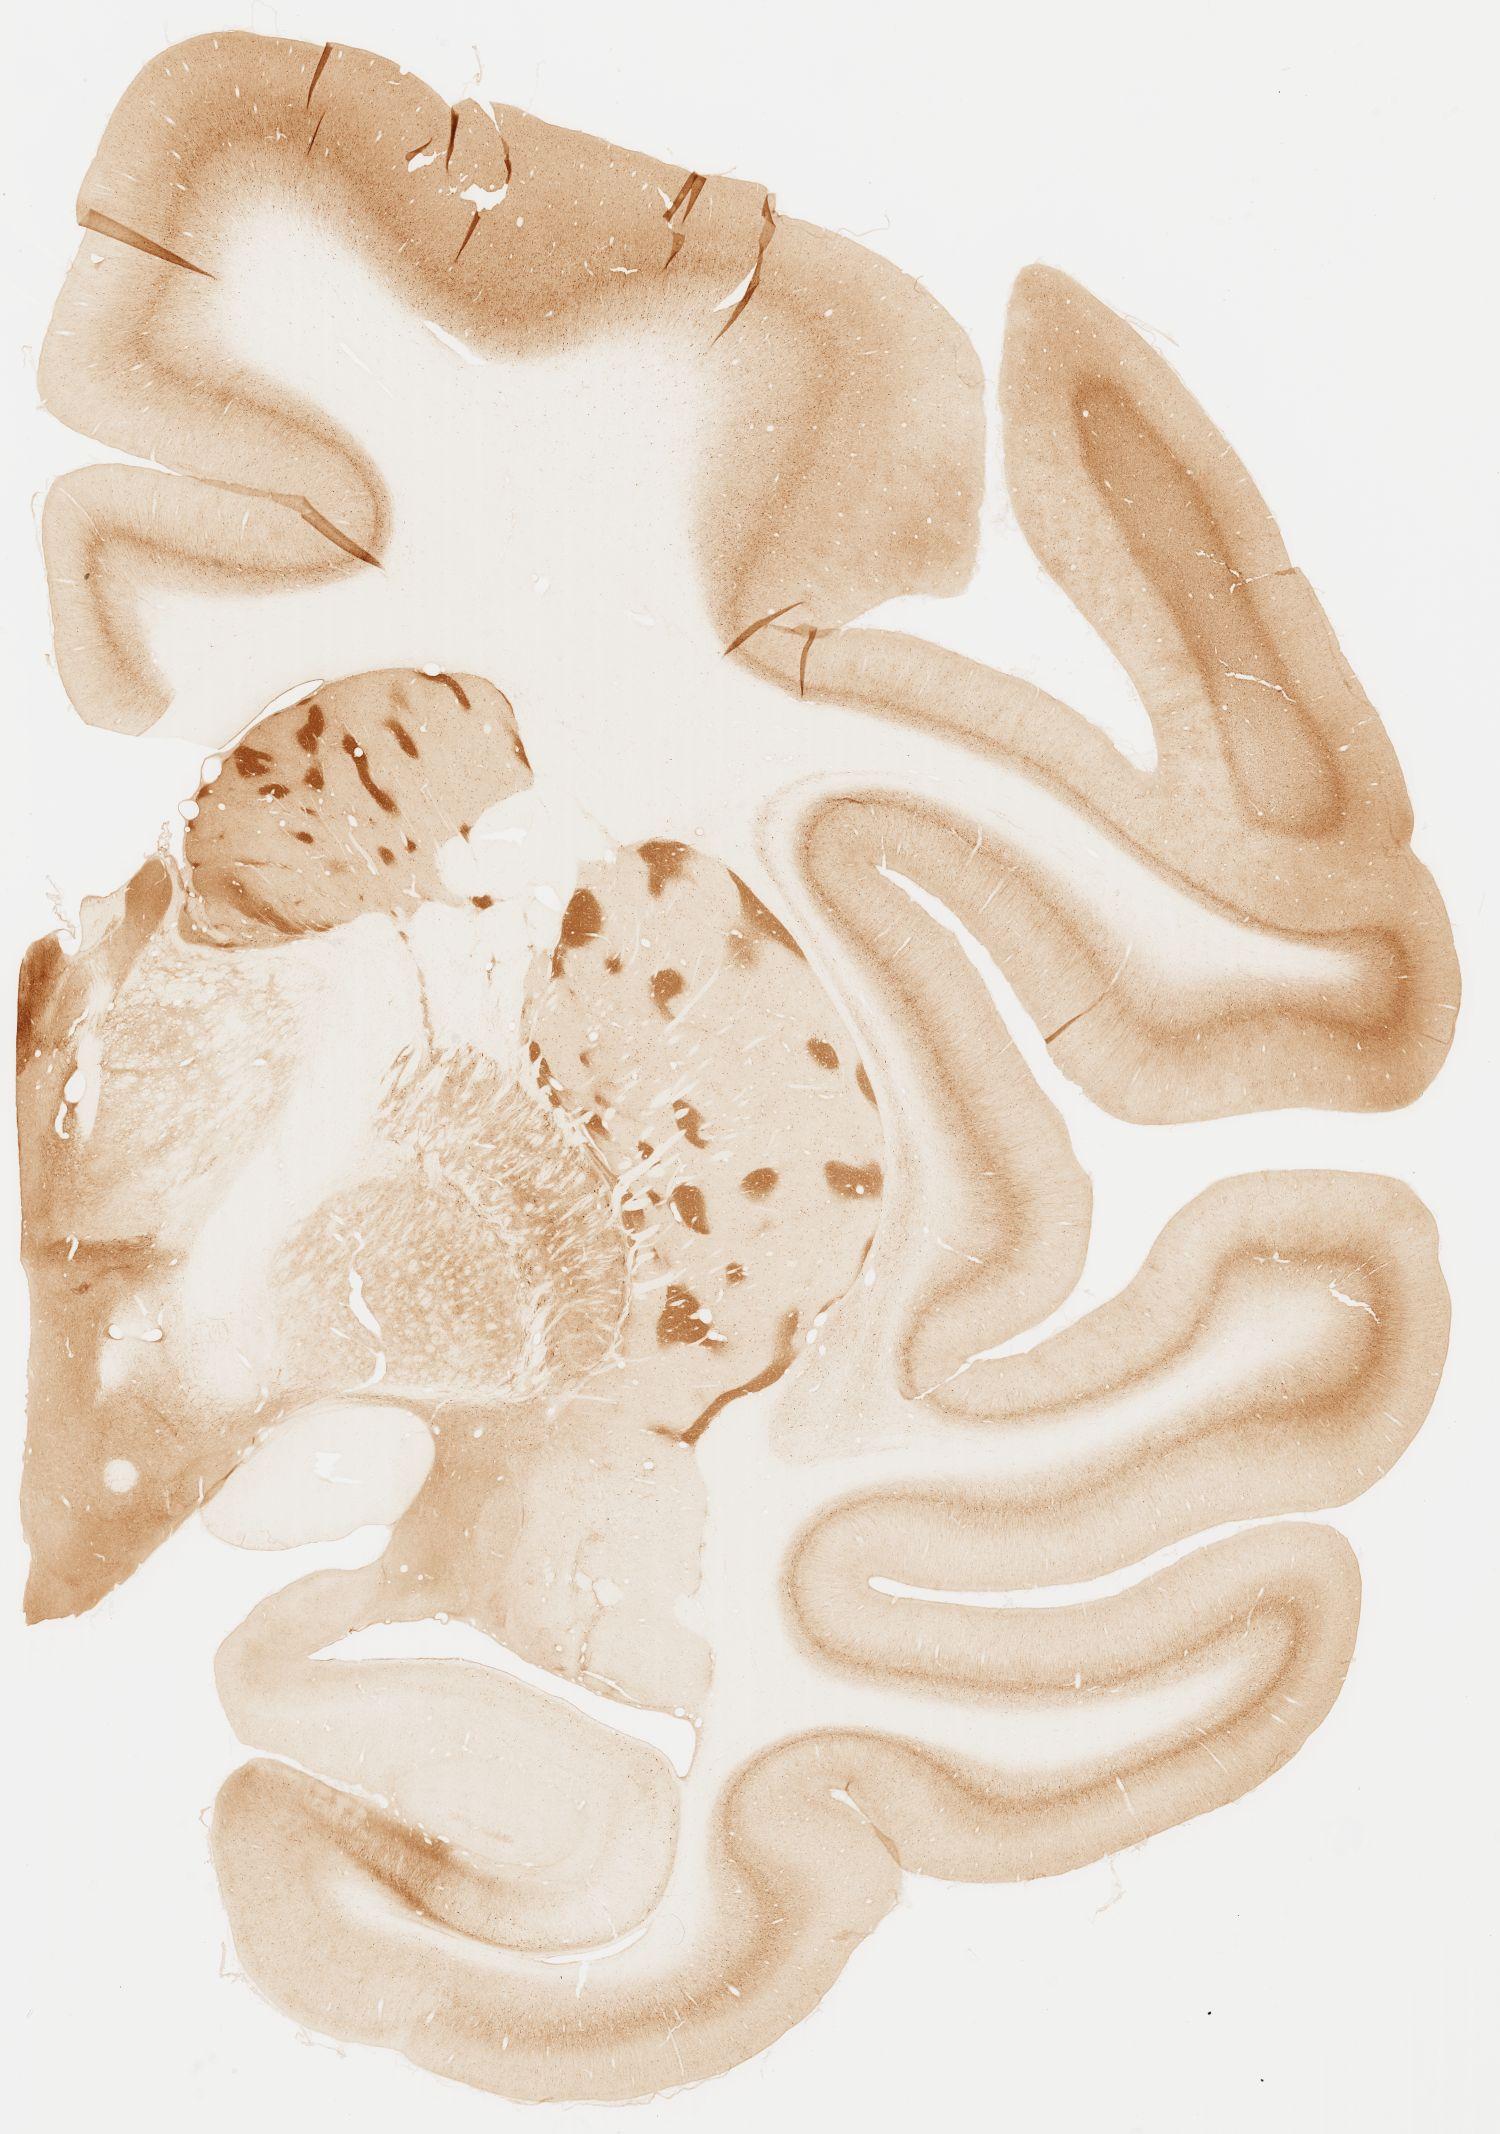

Datasets -> Macaca Fascicularis -> KChIP1, (Potassium Voltage-Gated Channel-Interacting Protein 1), coronal, immuno, Whole-Brain, adult

[ Metadata ]   ·   Source: Edward G. Jones

Displaying Sections 41 thru 80 of 92 Sections for this Dataset